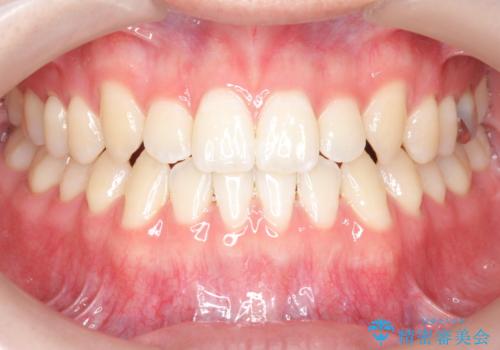

[ 前歯開咬 ] 前歯が噛んでいない マウスピース矯正治療

担当医 大元洋佑

![[ 前歯開咬 ] 前歯が噛んでいない マウスピース矯正治療の症例 治療後](https://seimitsushinbi.jp/wp/wp-content/uploads/2022/11/IMG_2488-500x350.jpg?v=1668218373)